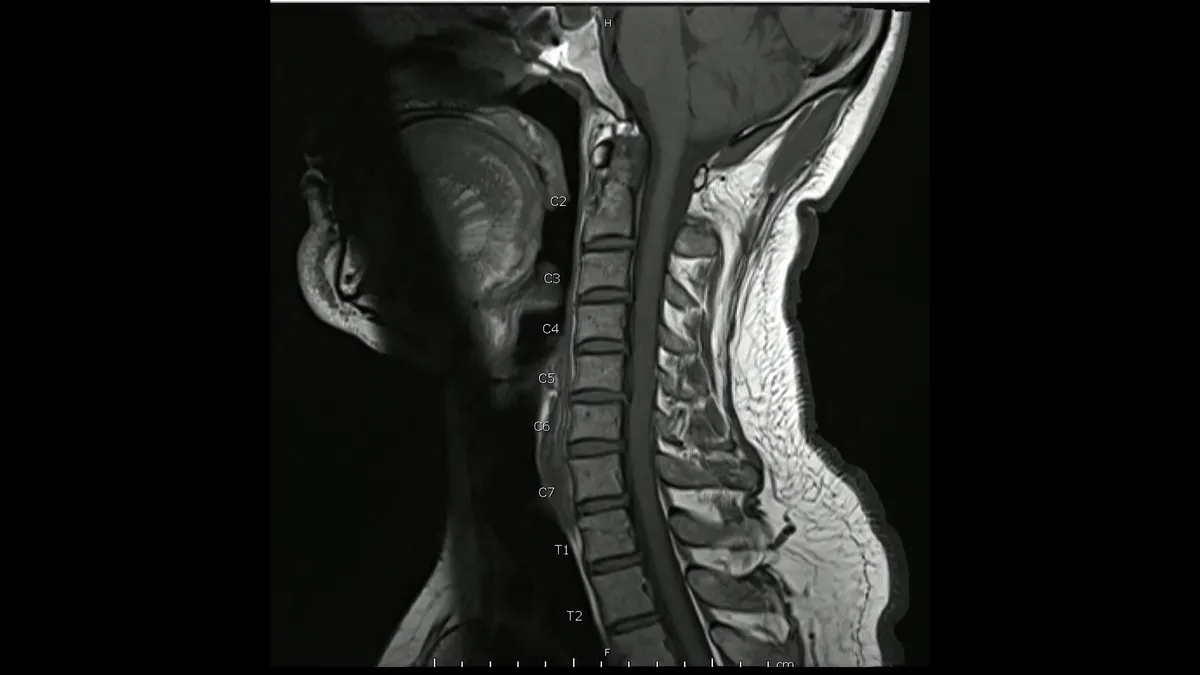

Spine surgeries are common procedures, but they often come with a long and painful recovery period. Despite recent advancements in technology, patients still frequently face complications such as failed healing and significant pain during recovery. To address this challenge, we are collaborating with Amir Alavi, PhD, to develop innovative spinal implants made from meta-tribomaterials.

These 3D-printable implants have properties that are computationally designed rather than inherent, allowing for precise control over their behavior to improve patient specificity. Additionally, the implants can harness the micromotions of the spine to generate biologically safe electrical energy. This energy can be used to monitor the forces acting on the spine and provide electrical stimulation, which helps expedite the healing process, reduce pain, and allow patients to return to their daily activities more quickly.